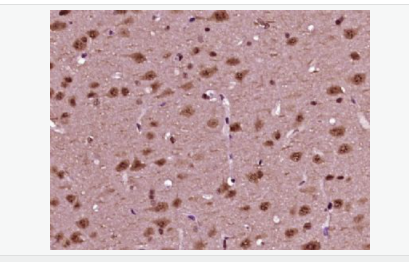

| 产品应用 | WB=1:500-2000 ELISA=1:5000-10000 IHC-P=1:100-500 IHC-F=1:100-500 ICC=1:100-500 IF=1:100-500 (石蜡切片需做抗原修复) not yet tested in other applications. optimal dilutions/concentrations should be determined by the end user. |

| 细胞定位 | 细胞核 细胞浆 |